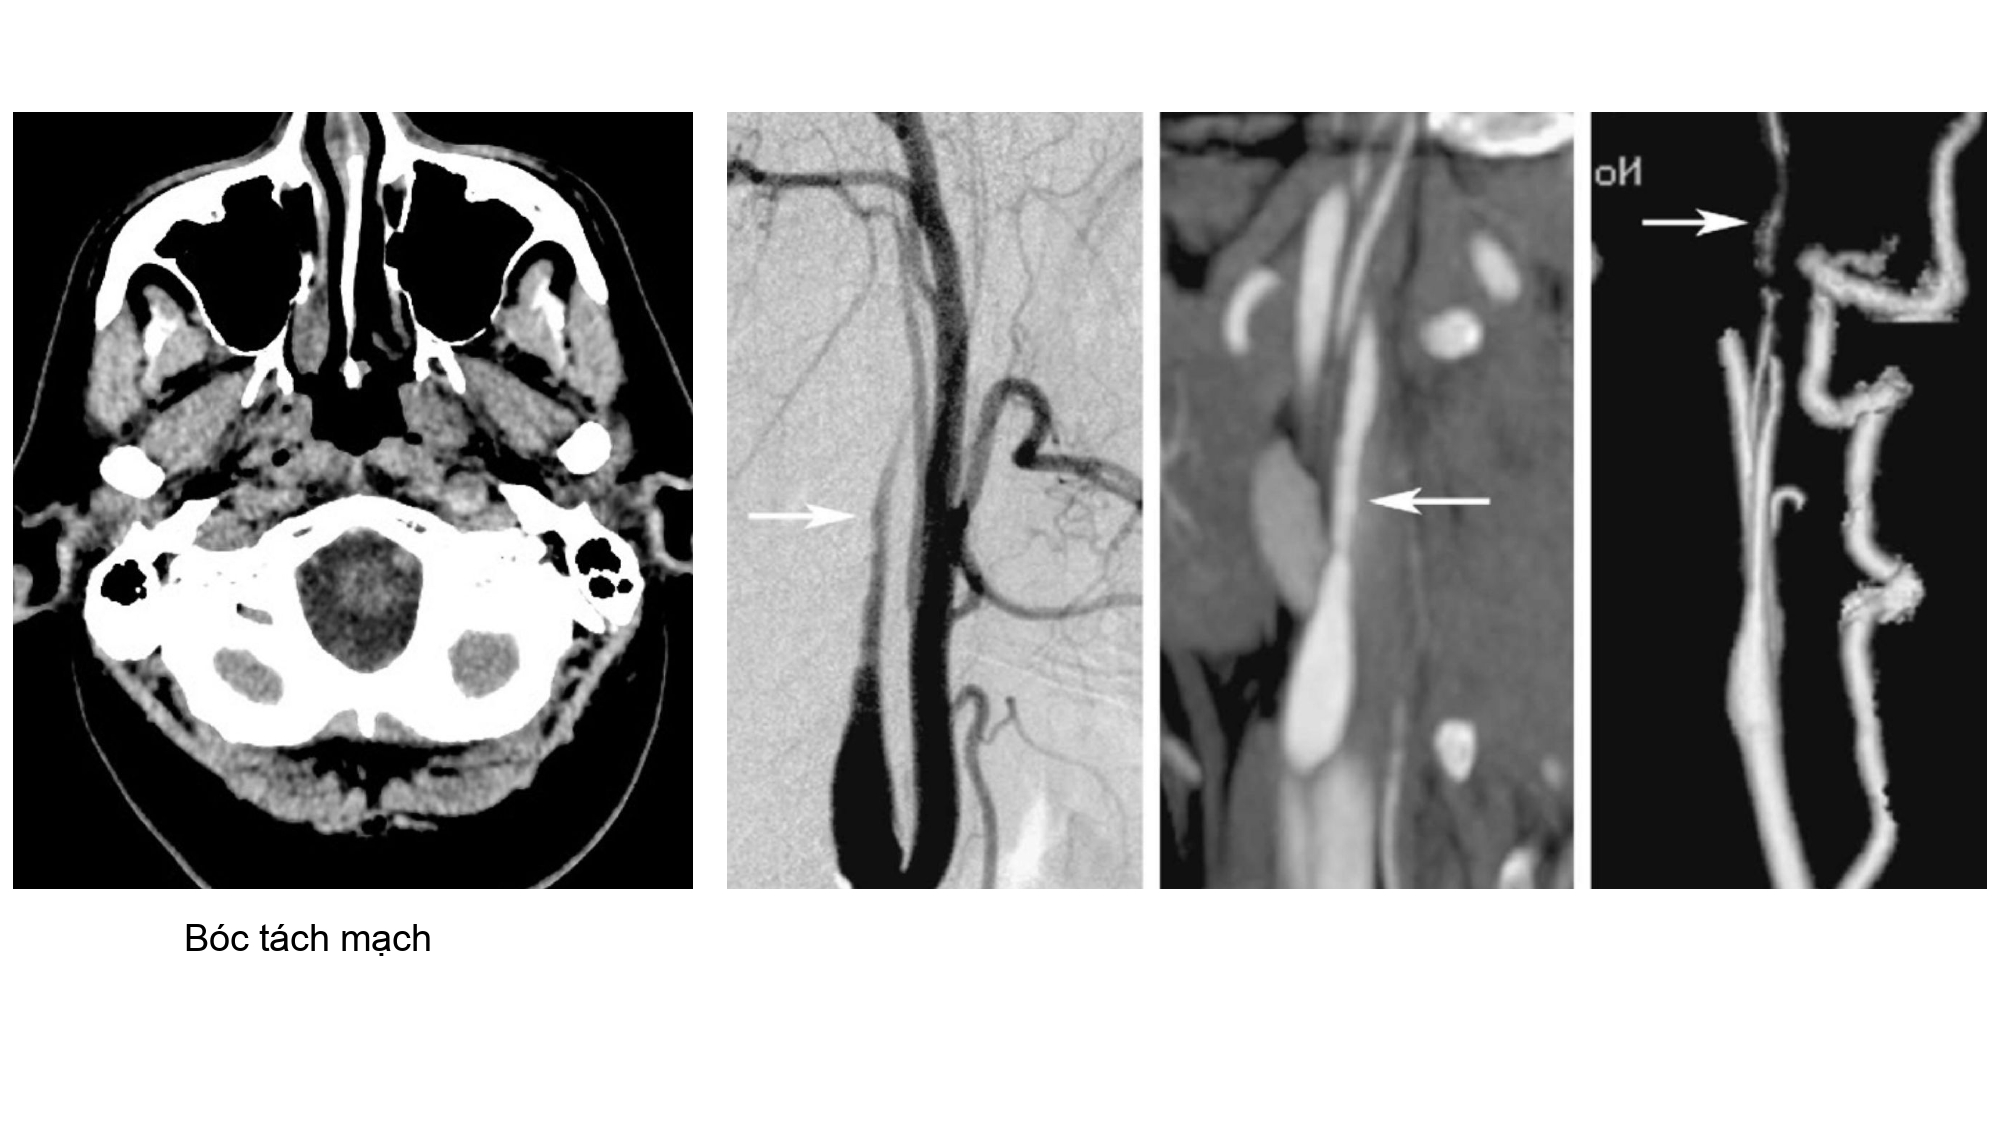

| 13:30 - 14:10 | Surgical management of skull base trauma Endovascular Management of Post-Traumatic Intracranial Vascular Lesions | Assoc. Prof. Nguyen Trong Yen Dr. Nguyen Ngoc Cuong | |